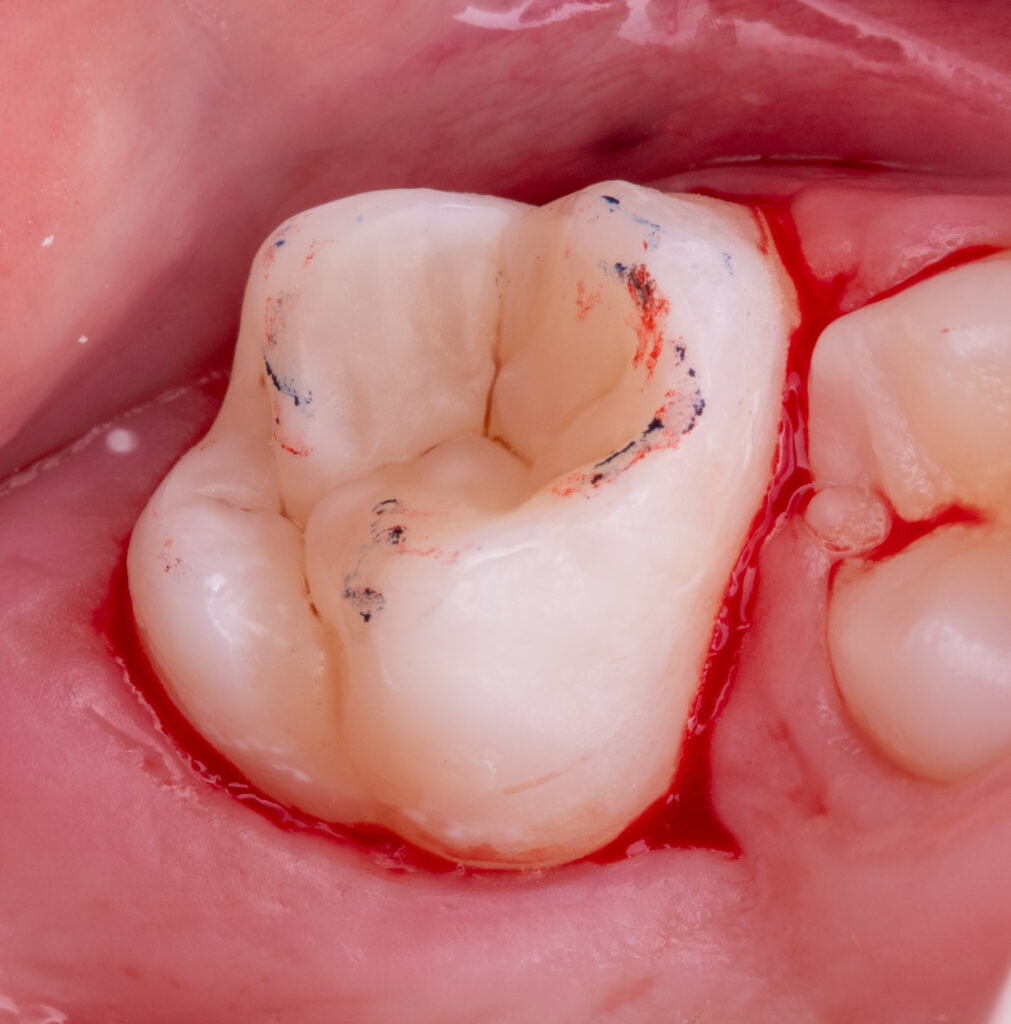

In a single visit, the old composite restoration was completely removed and replaced with a new composite (Asteria A2B / NeoSpectra A2).

EverX (flowable glass fiber composite) was used as a reinforcing layer to improve the strength and durability of the tooth.

Total treatment time: 50 minutes.